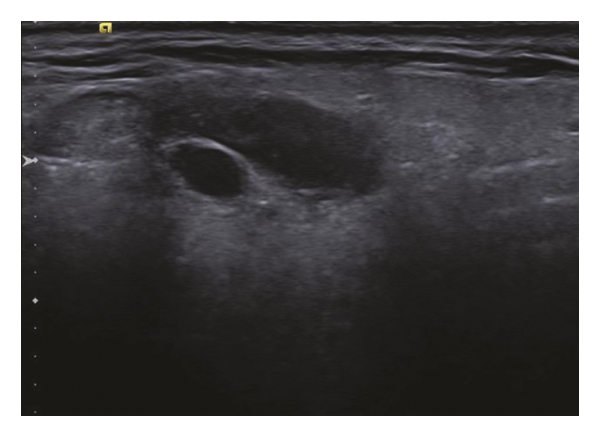

The patient returned and noted some residual right facial swelling. The mass was nontender, and the patient denied dysphagia or pain with chewing. Of note, the patient had not traveled and had no further infectious exposures. An ultrasound was performed and revealed a residual 1.9 × 0.9 × 0.8 cm hypoechoic lesion within the right parotid gland (Figure 3). A repeat FNA was performed and yielded another 2 cc of clear fluid with only secretory debris without evidence of a cestode. At this time, further workup was offered including potential surgical excision, but the patient wished to defer this due to continued travel plans.